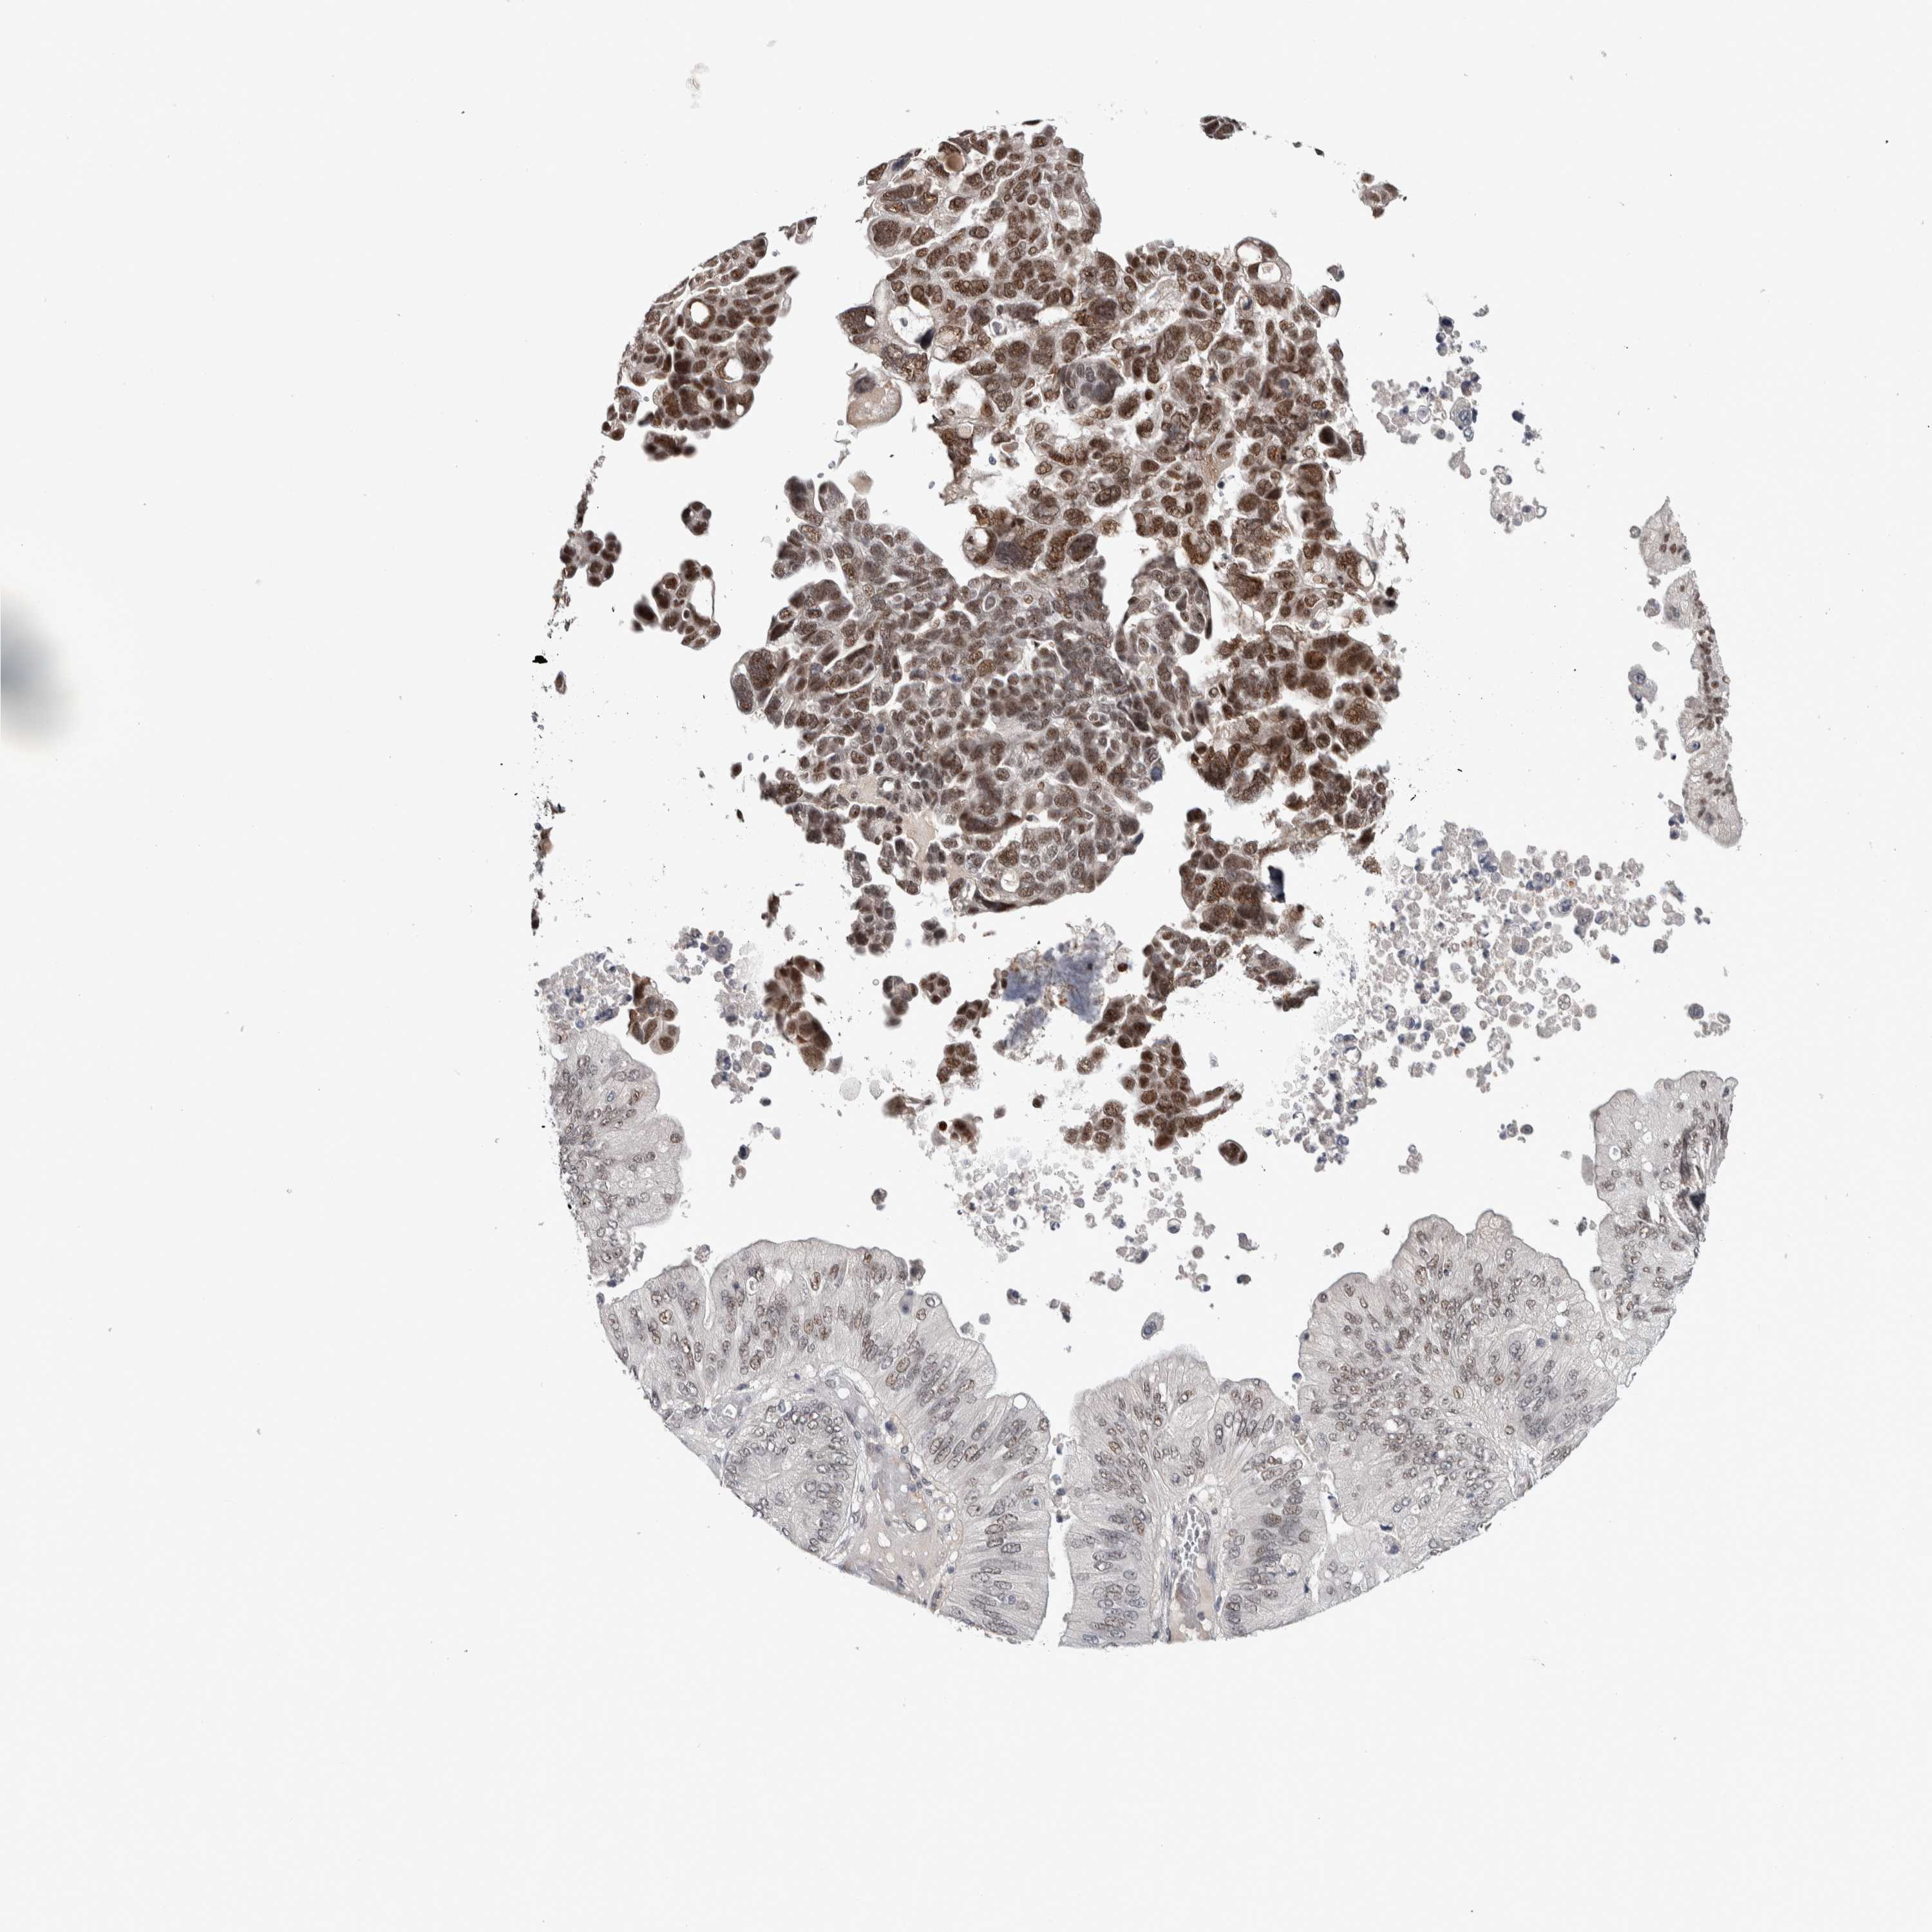

OVARIAN CANCER - Protein expressioni

A mouse-over function shows sample information and annotation data. Click on an image to view it in a full screen mode. Samples can be filtered based on level of antibody staining by selecting one or several of the following categories: high, medium, low and not detected. The assay and annotation is described here.

Note that samples used for immunohistochemistry by the Human Protein Atlas do not correspond to samples in the TCGA dataset.

Antibody stainingi

Antibody staining in the annotated cell types in the current human tissue is reported as not detected, low, medium, or high, based on conventional immunohistochemistry profiling in selected tissues. This score is based on the combination of the staining intensity and fraction of stained cells.

Each image is clickable and will lead to virtual microscopy that enables deeper exploration of all samples and also displays staining intensity scores, fraction scores and subcellular localization as well as patient and tissue information for each sample.

Antibody HPA008435

Antibody HPA024230

Staining

High

Medium

Low

Not detected

Intensity

Strong

Moderate

Weak

Negative

Quantity

>75%

75%-25%

<25%

None

Location

Nuclear

Cytoplasmic/membranous

Cytoplasmic/membranous,nuclear

Cystadenocarcinoma, serous, NOS

Carcinoma, endometroid

Cystadenocarcinoma, mucinous, NOS

Carcinoma, NOS